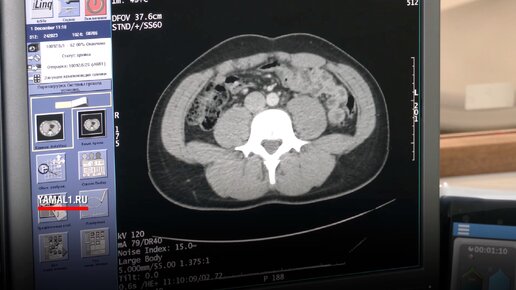

Ямальский онколог назвал топ органов, рак которых чаще всего диагностируют у северян